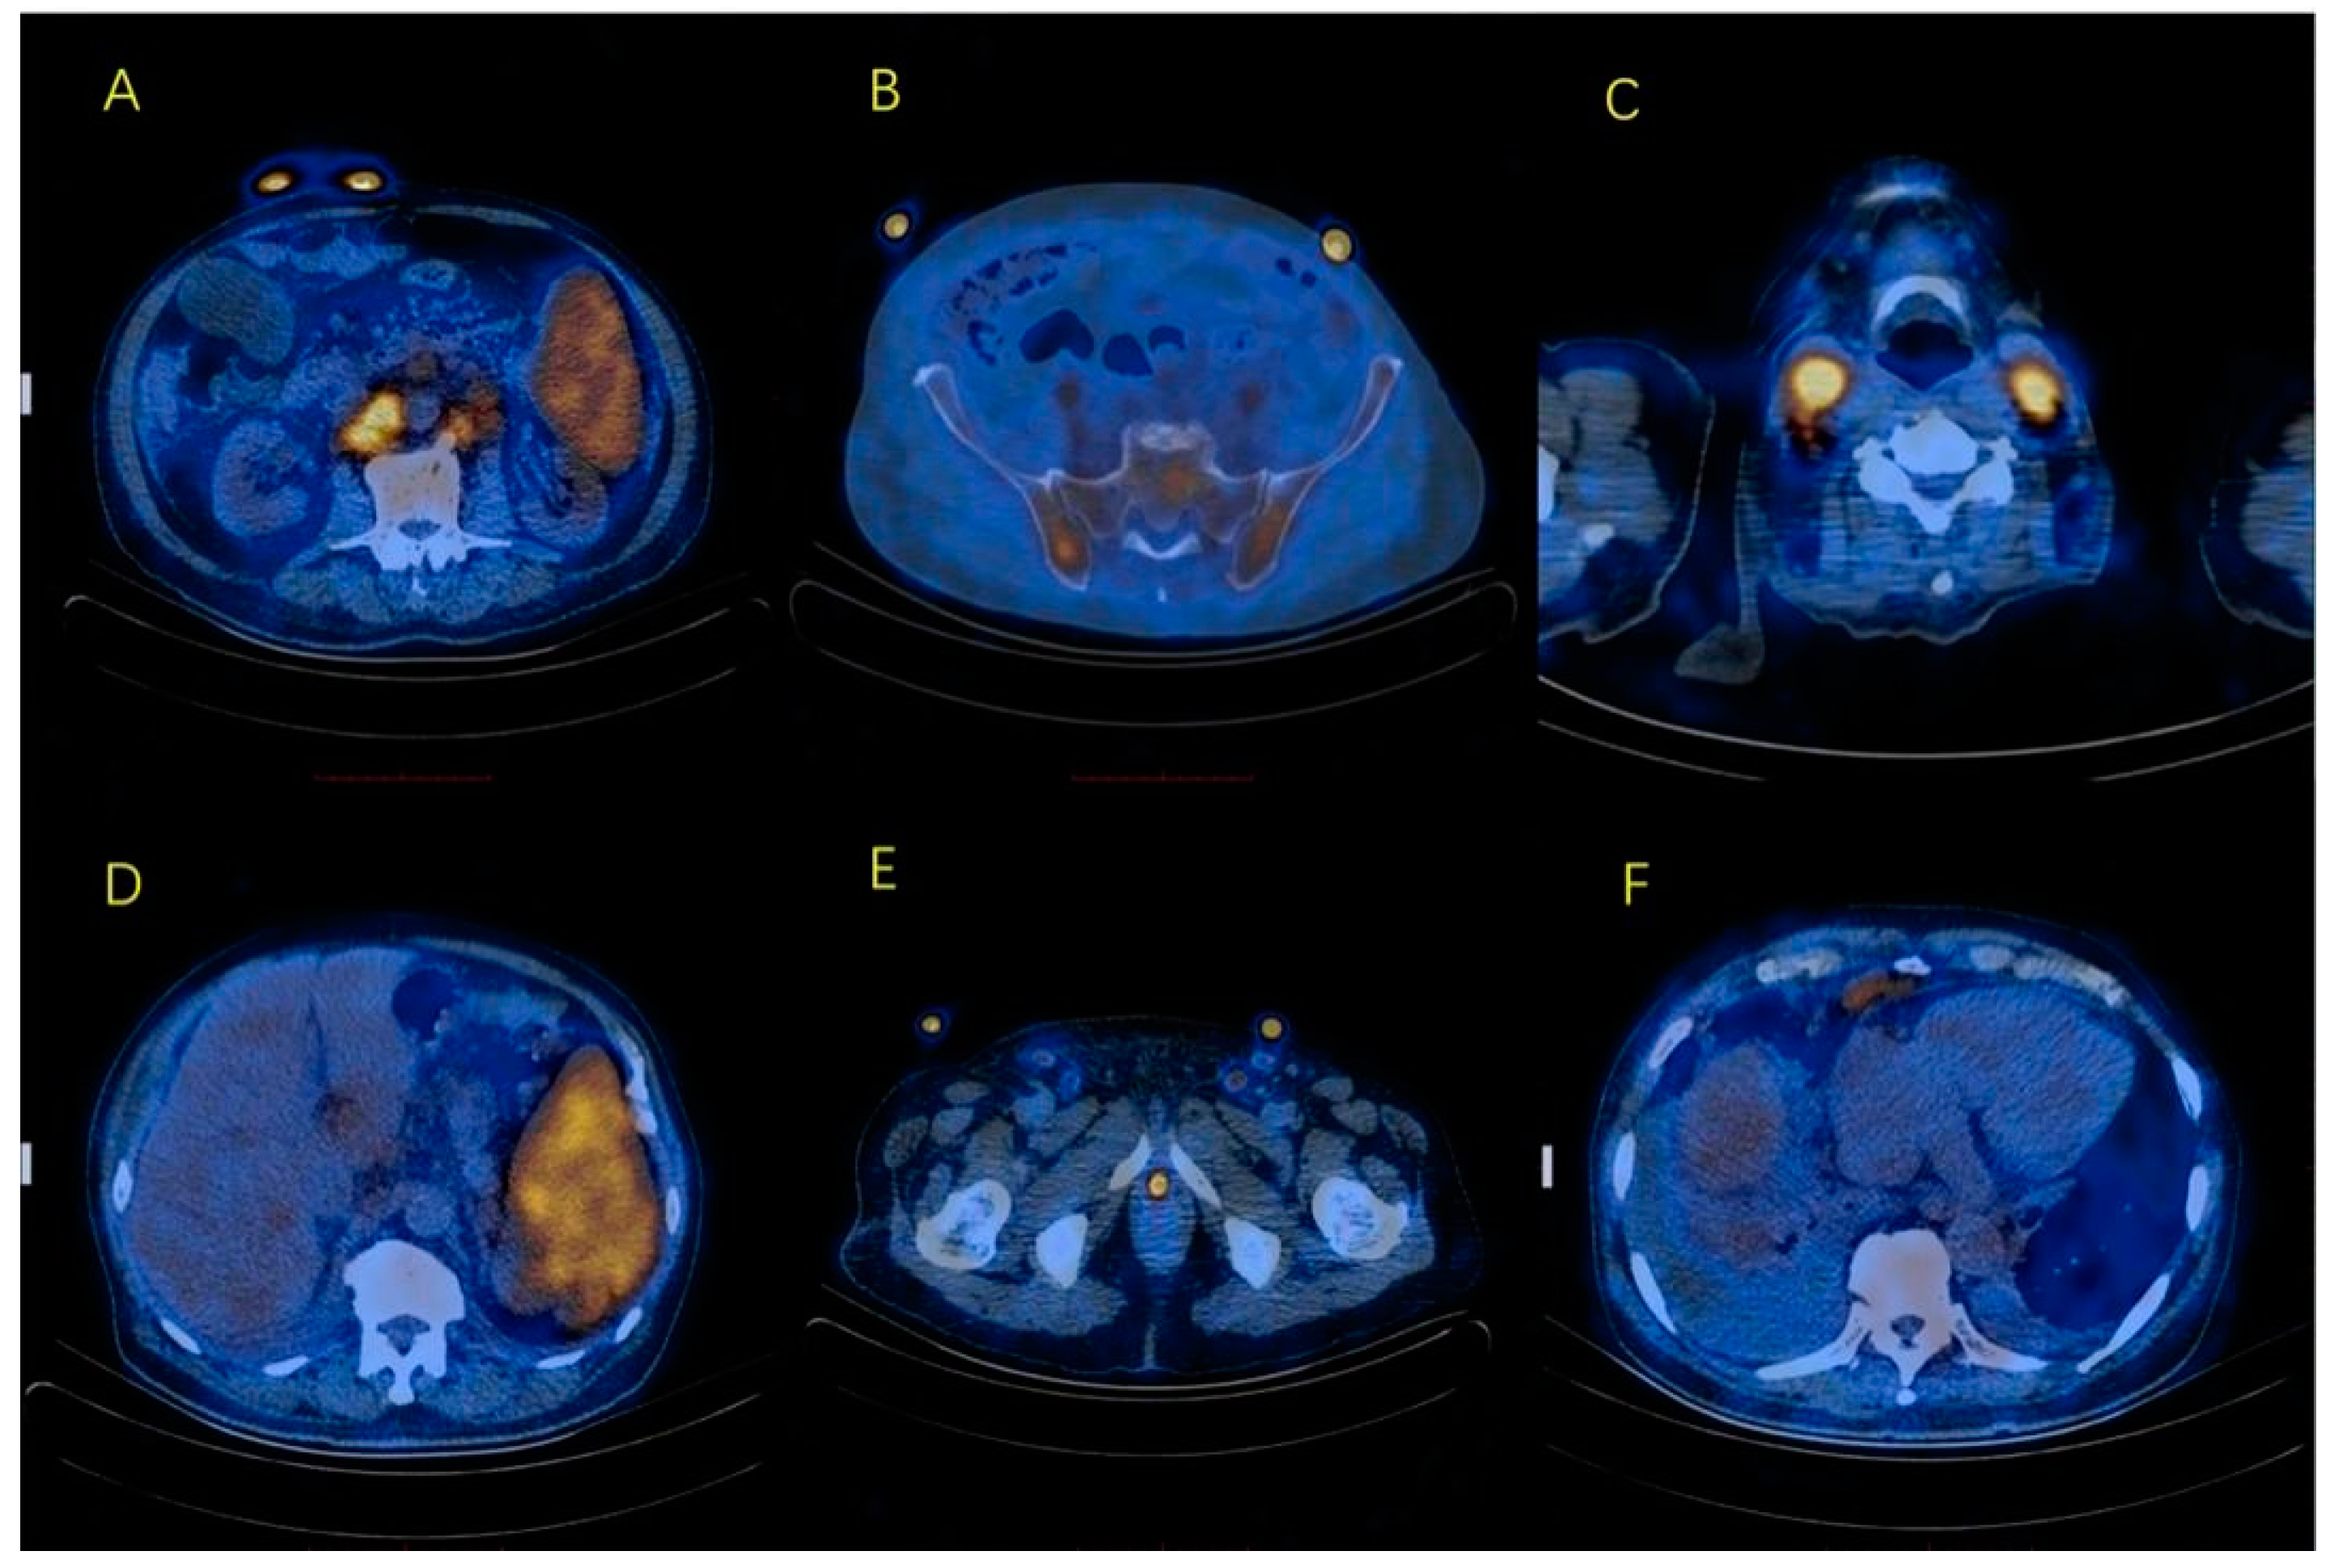

2. Case Presentation